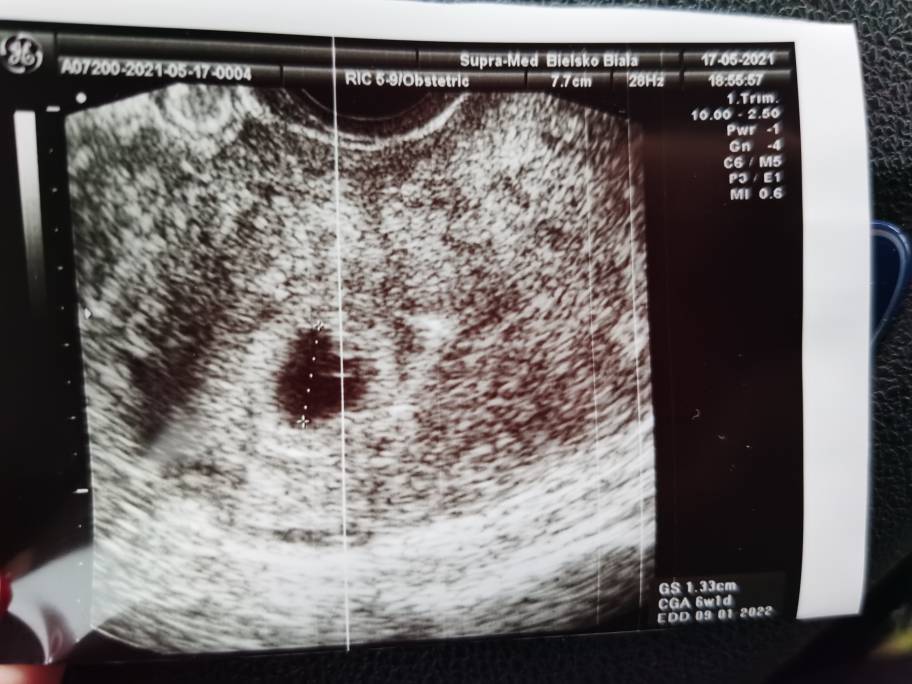

Dziewczyny widziałam [emoji3590] normalnie prawie się popłakałam, tydzień dokładnie taki jak mi pokazywali w aplikacji czyli 6+1, kolejna wizyta 14.06 [emoji3059][emoji3059][emoji3059]

IMG_20210517_185908.jpeg

Dziewczyny widziałam [emoji3590] normalnie prawie się popłakałam, tydzień dokładnie taki jak mi pokazywali w aplikacji czyli 6+1, kolejna wizyta 14.06 [emoji3059][emoji3059][emoji3059]Zobacz załącznik 1272543

Lekarz mnie zapisał już na prenatalne na 29.06, dostałam badania do wykonania i na następnej wizycie założymy kartę ciąży. Ogólnie dużo stresu przed wizytą, ale najważniejsze że jest wszystko dobrze i widziałam kropkę i to pulsujace serduszko [emoji3590]